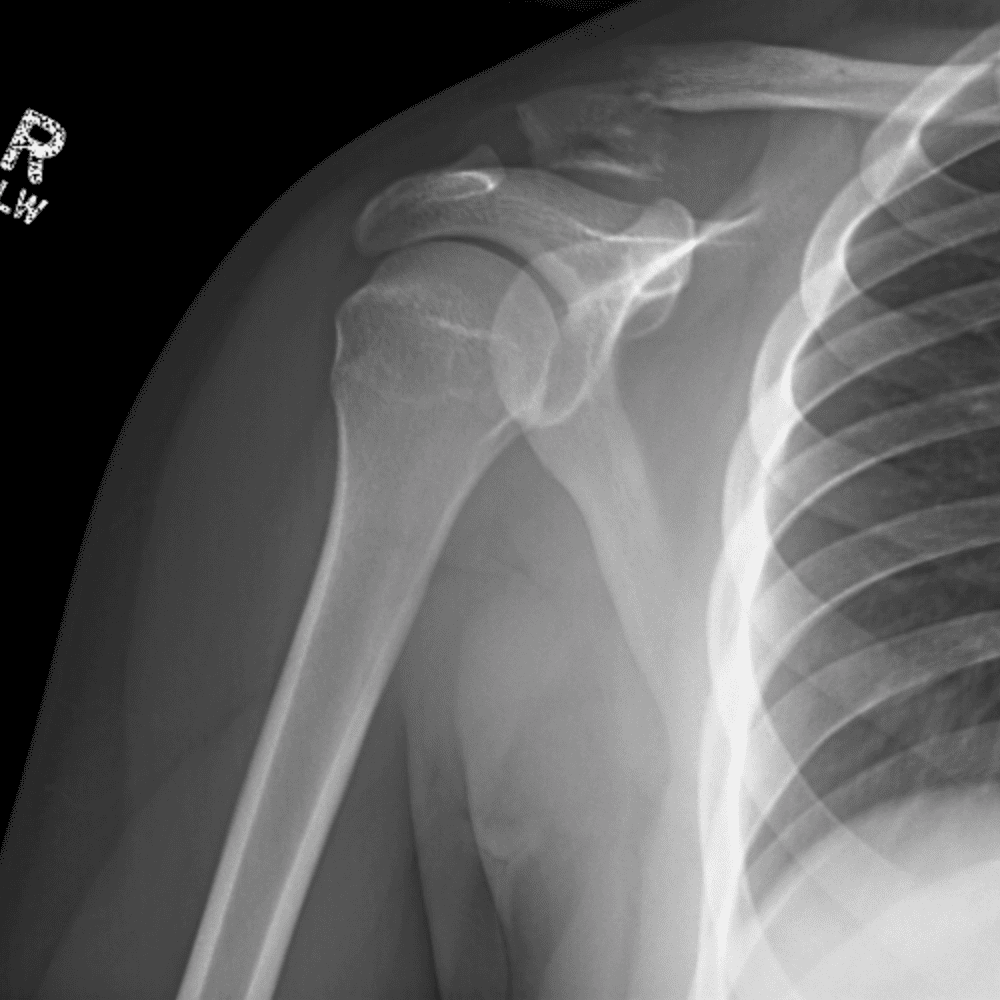

Simuliert den Dienst durch subtile oder schwierige Fälle und einige Normalbefunde.

30 Fälle